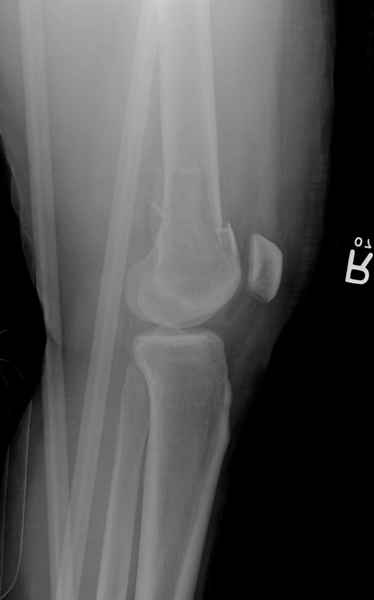

Уважаемые коллеги! От имени Алексея Смирнова всем спасибо за обсуждение. Больной прооперирован. Снимки в приложении.

Мы бы не стали открывать, такие переломы срастаются, хотя бы и с краевым дефектом. То есть если удалять стержень потом, то сильно попозже обычного. В приложении пример. Сразу после операции и через 11 мес. Понятное дело, пациент к тому времени давно и не хромал, и функция колена была полная.